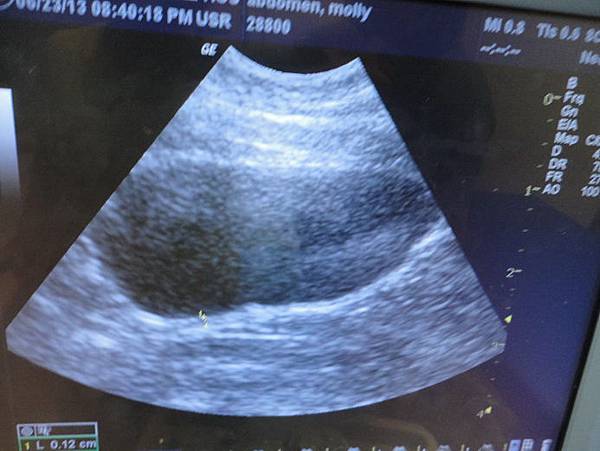

先看了膀胱,膀胱沒有明顯亮亮的結晶或是石頭

超音波下的肝臟也還ok

膽囊沒有明顯的膽泥

但是在脾臟有看到兩個很小的不明亮點

醫生有說可以再約診找黃醫師做確認